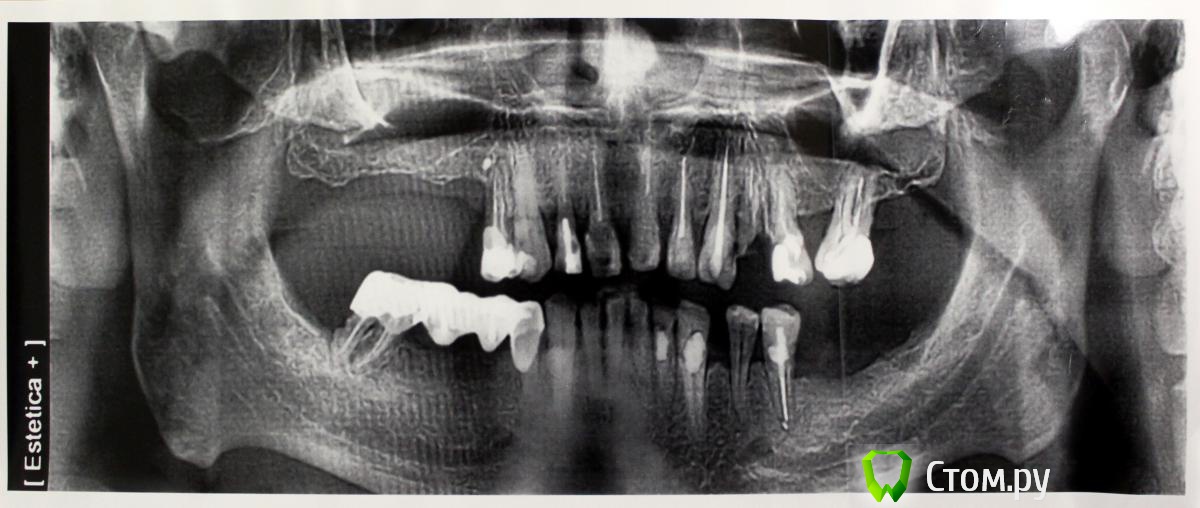

Привет всем! уважаемые Гуру помогите с планированием реабилитации данного пациента. Основная жалоба, не хочет носить съемный протез (пришел из другой клиники, где рекомендовали только съемное протезирование).

Провели обследование. Ортопед планирует оставить вверху 6 фронтальных зубов (возможно резцы пойдут на удаление), внизу только клыки. Далее последует удаление несостоятельных зубов + иммедиат протезы, продолжение реабилитации.

1. правильно ли я понимаю, что через 1,5 - 2 месяца после удаления 1.4 можно провести аугментацию (синус-лифтинг, латеральное окно, в первом сегменте, возможно с одномоментной установкой имплантатов)?

2. нужна ли в 1 сегменте дополнительная аугментация (по вертикали)?

3. в какие позиции должны быть поставлены имплантаты в 1 сегменте сбоку (1.7, 1.5)?

4. через 1,5 - 2 месяца после удаления 4.4 и 4.7 провести установку имплантатов в 4 сегменте?

5. в какие позиции должны быть поставлены имплантаты в 4 сегменте сбоку (4.5, 4.7?)?

6. через какой промежуток времени после удаления зубов 3.4, 3.5 проводить аугментацию в 3 сегменте? какая аугментация предпочтительнее? в какие позиции должны быть поставлены имплантаты (3.4, 3.6?)?

7. через 2-3 месяца после удаления 2.4, 2.5, 2.6 провести открытый синуслифтинг во втором сегменте возможно с одномоментной установкой имплантатов?

8. в какие позиции должны быть поставлены имплантаты во 2 сегменте (2.5, 2.6?)?

9. через 3 месяца после удаления 1.2, 1.1, 2.1, 2.2, 3.2, 3.1, 4.1, 4.2 зубов провести установку имплантатов во фронтальном отделе нижней, возможно верхней челюстей в позиции 1.2, 2.2 + 3.2, 4.2?